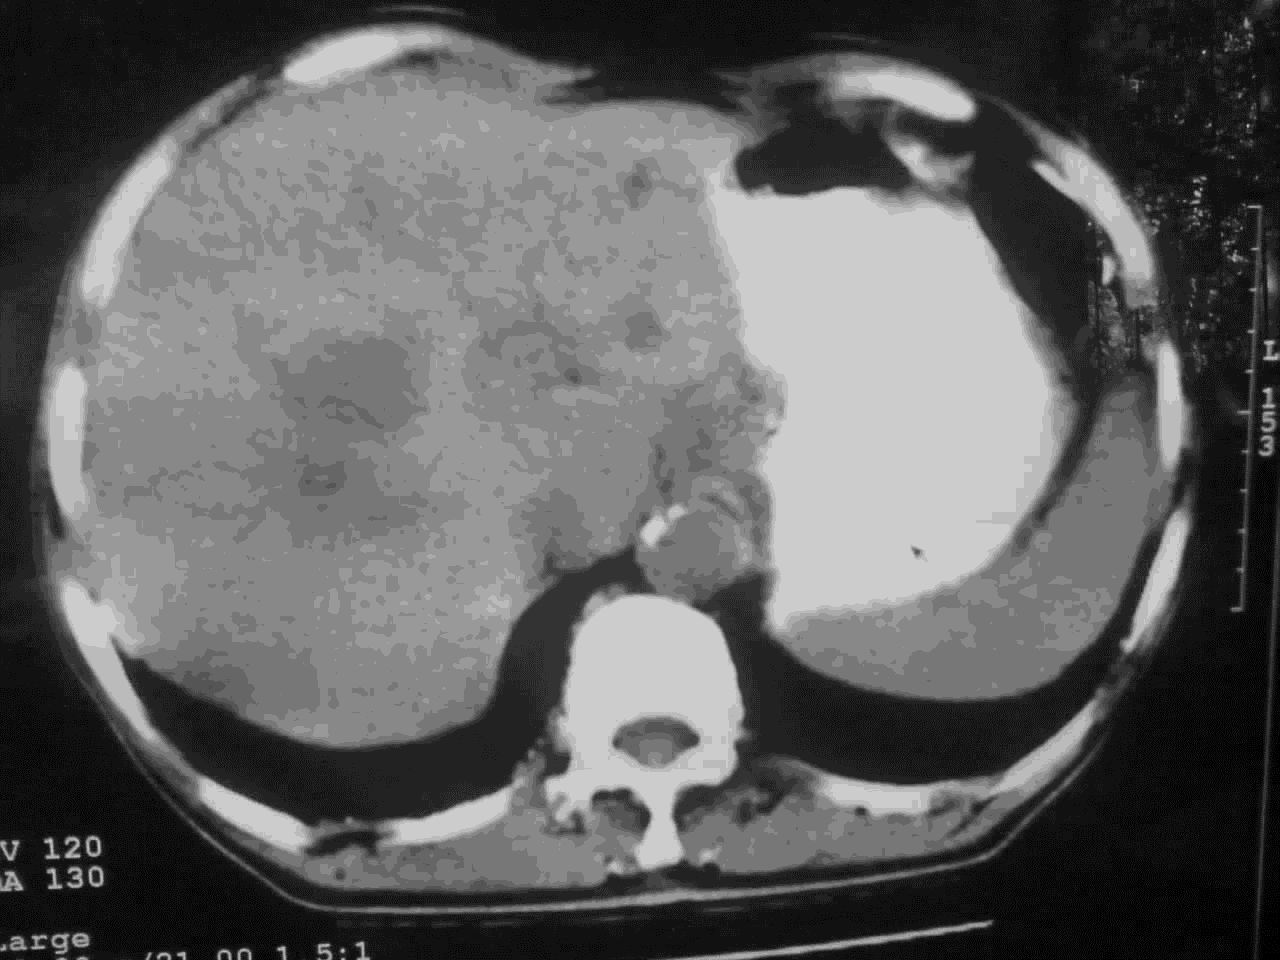

好象是横结肠占位肝转移,胰头占位?【伙计,您的片也真够意思】

横结肠占位肝转移

好象是横结肠占位肝转移,胰头占位?

考虑升结肠癌伴肝转移;胆囊炎。

好象是横结肠占位肝转移.

结肠占位并肝及腹膜后淋巴结转移。

考虑升结肠癌伴肝转移;胆囊炎